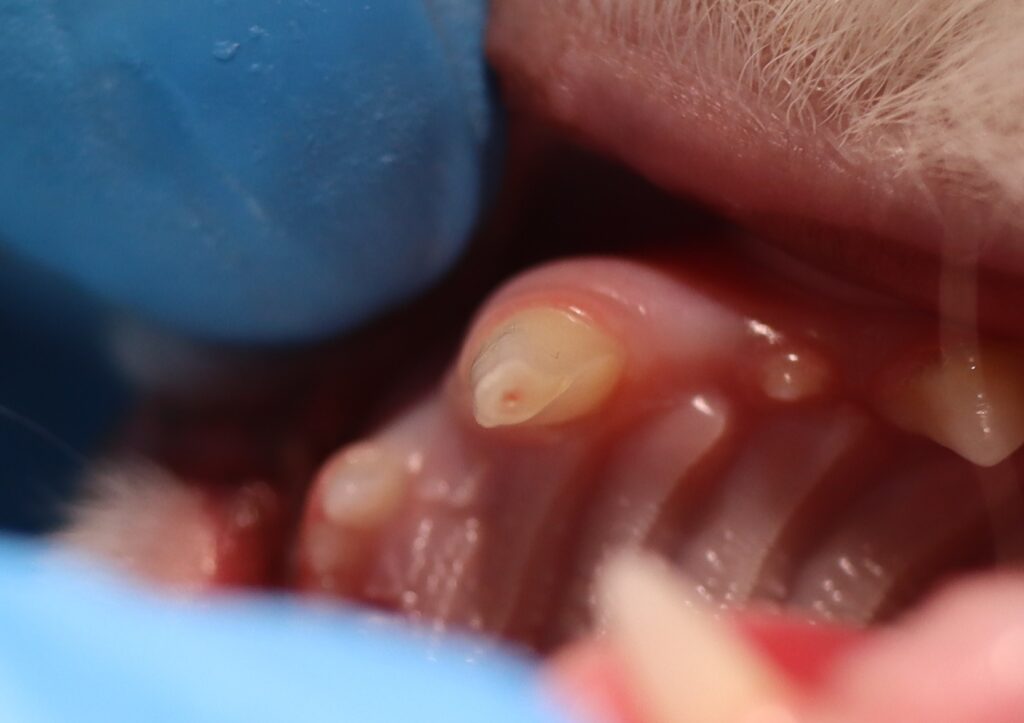

今回の症例は、左上犬歯が折れてしまった猫です。

毎日歯磨きをしている子で、折れたのは確実に1日前、そしてその日に治療を行うことができました。

- レントゲン検査では根尖病変は認められず

- 破折直後で、歯髄も止血可能な状態

- 条件を満たしていたため、生活歯髄切断術を実施しました